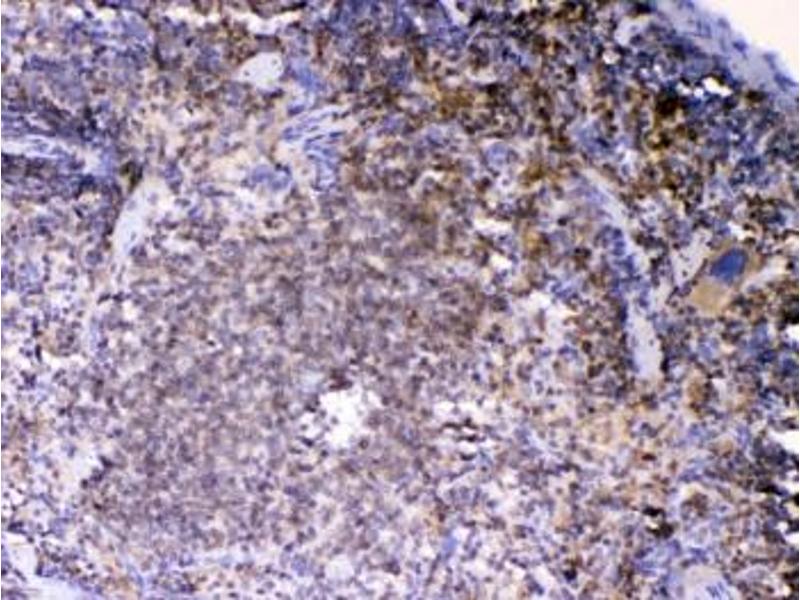

LYN Antikörper (AA 470-501)

Dieser Kaninchen Polyklonal Antikörper detektiert spezifisch LYN in WB und IHC (p). Es zeigt Reaktivität gegenüber Proben von Human, Maus und Ratte.

Western Blotting (WB), Immunohistochemistry (Paraffin-embedded Sections) (IHC (p))